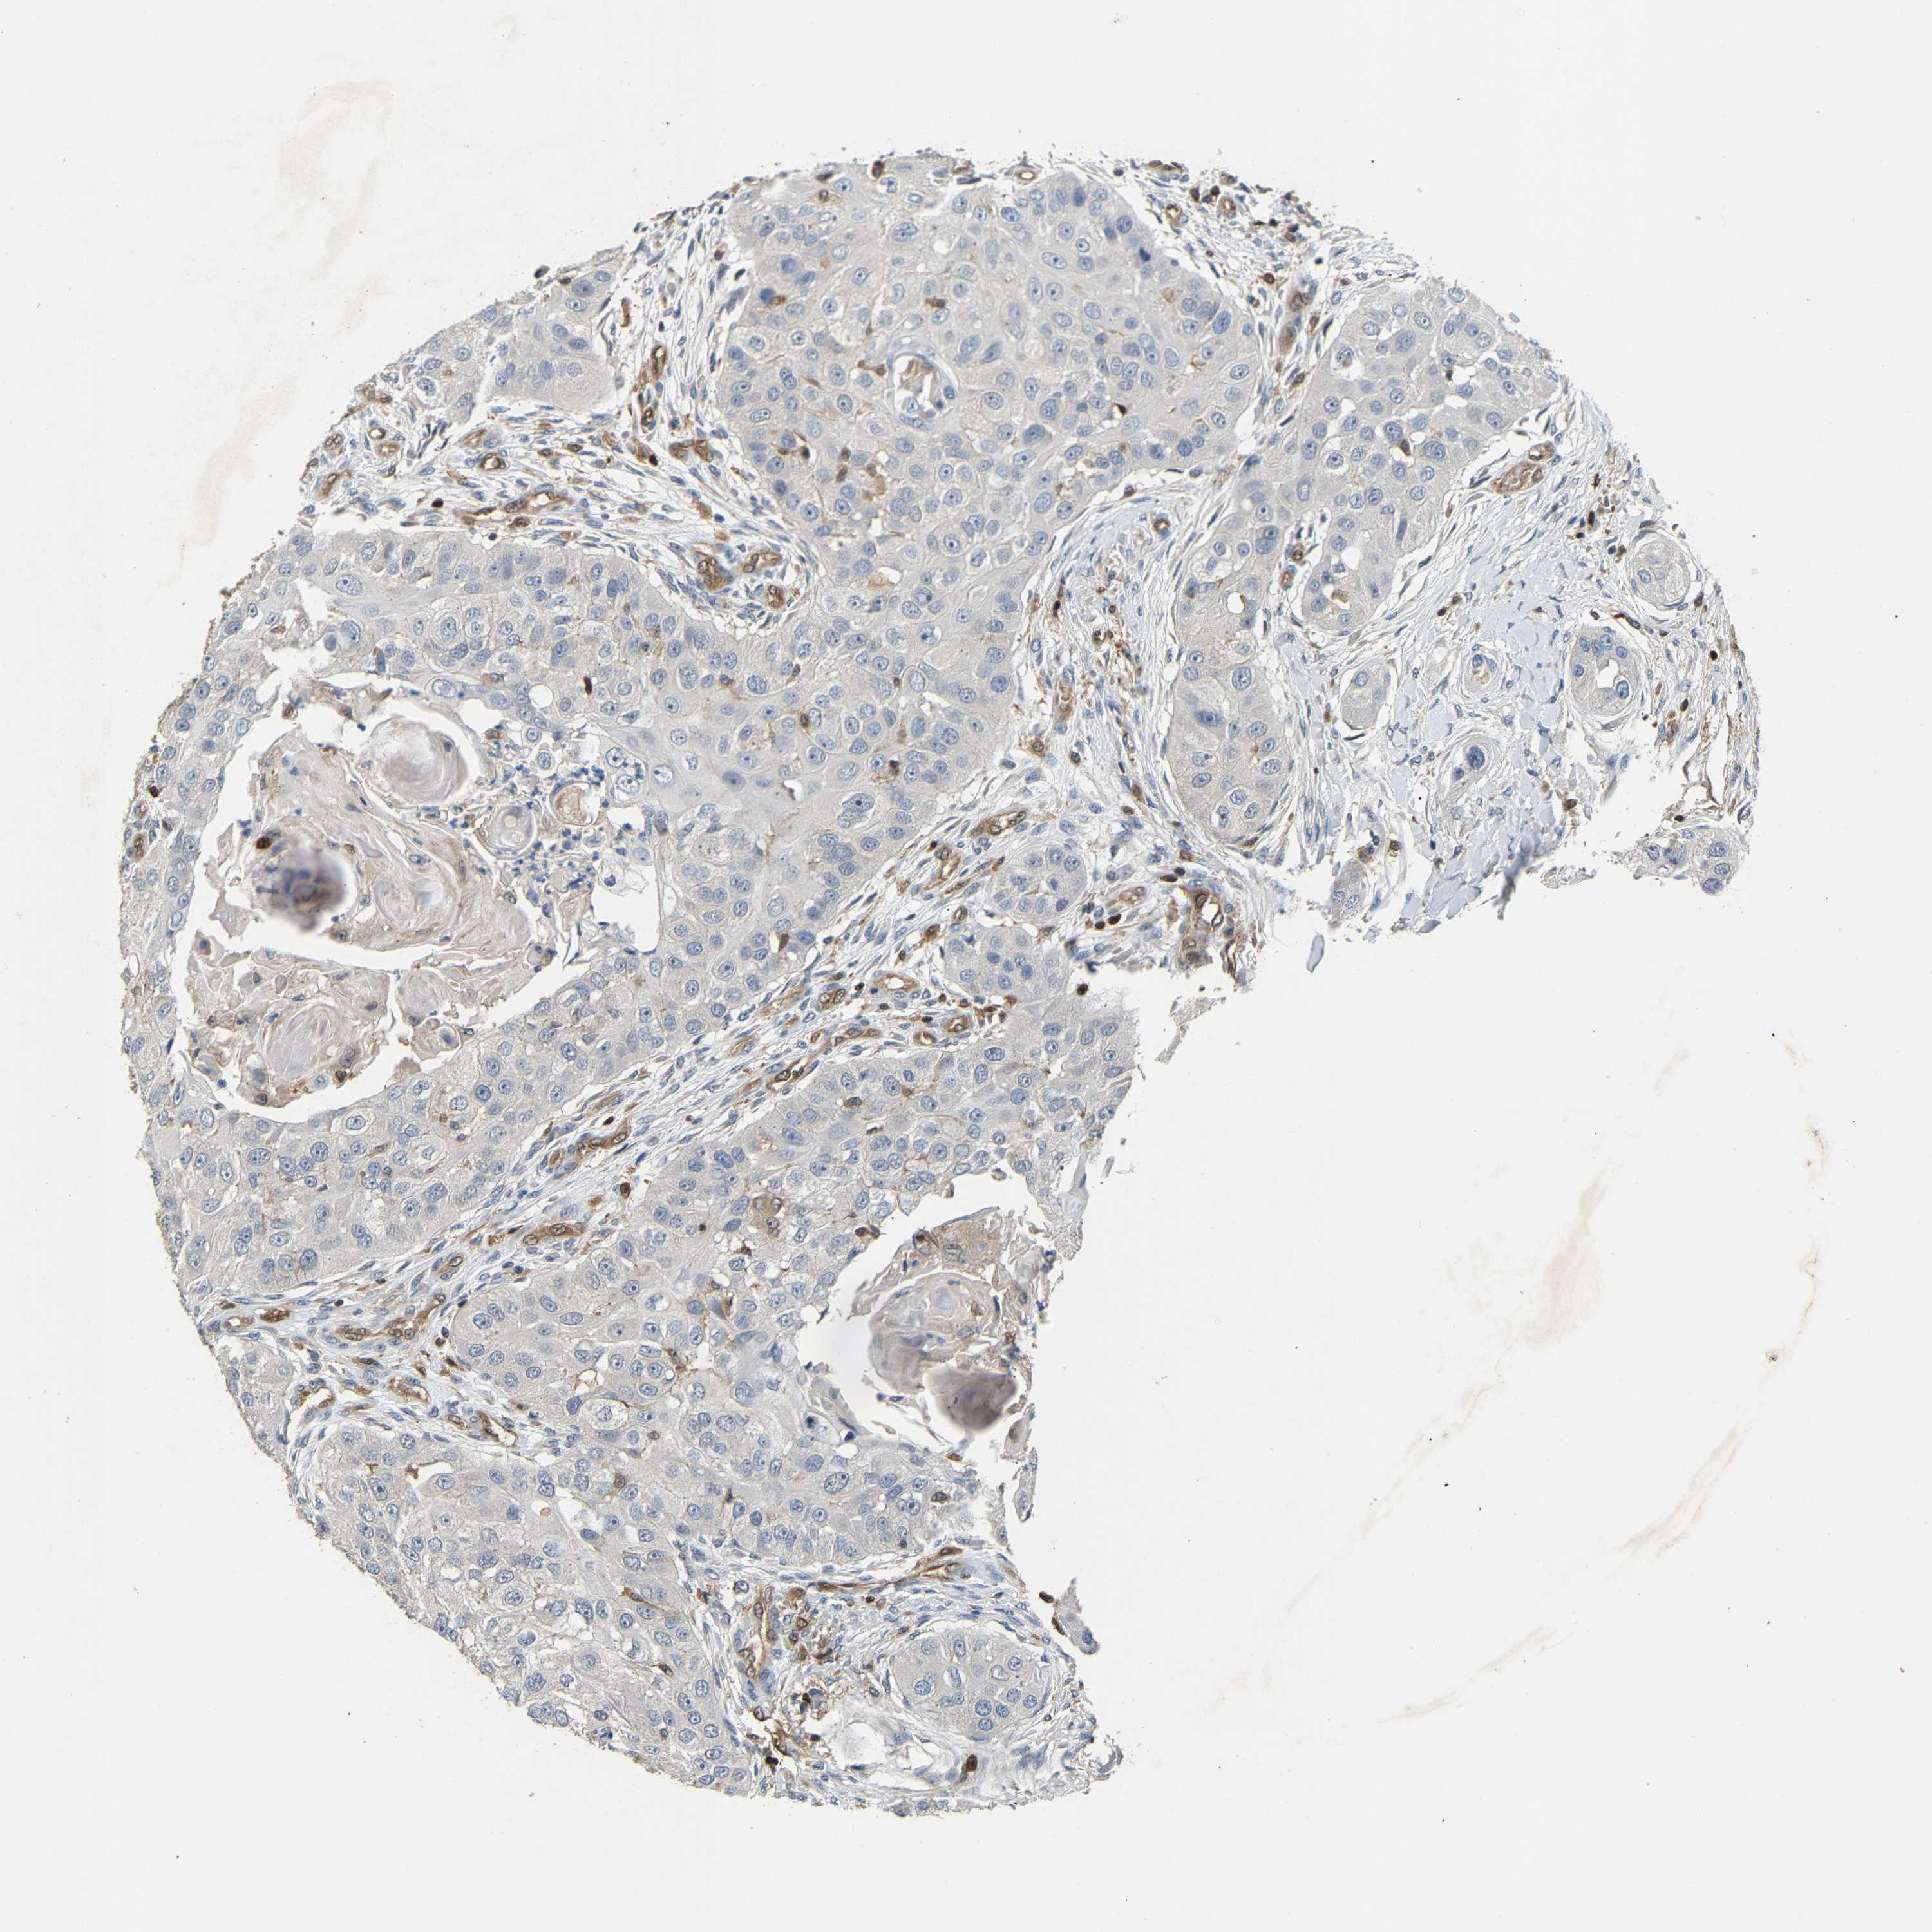

HEAD AND NECK CANCER - Protein expressioni

A mouse-over function shows sample information and annotation data. Click on an image to view it in a full screen mode. Samples can be filtered based on level of antibody staining by selecting one or several of the following categories: high, medium, low and not detected. The assay and annotation is described here.

Note that samples used for immunohistochemistry by the Human Protein Atlas do not correspond to samples in the TCGA dataset.

Antibody stainingi

Antibody staining in the annotated cell types in the current human tissue is reported as not detected, low, medium, or high, based on conventional immunohistochemistry profiling in selected tissues. This score is based on the combination of the staining intensity and fraction of stained cells.

Each image is clickable and will lead to virtual microscopy that enables deeper exploration of all samples and also displays staining intensity scores, fraction scores and subcellular localization as well as patient and tissue information for each sample.

Antibody HPA020266

Antibody HPA020268

Staining

High

Medium

Low

Not detected

Intensity

Strong

Moderate

Weak

Negative

Quantity

>75%

75%-25%

<25%

None

Location

Nuclear

Cytoplasmic/membranous

Cytoplasmic/membranous,nuclear

Squamous cell carcinoma, NOS

Squamous cell carcinoma, metastatic, NOS

Adenocarcinoma, NOS